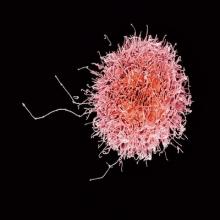

A new type of immunotherapy showed promising results in a small trial done by the MD Anderson Cancer Center. The researchers used an immune cell called a Natural Killer (NK) cell. The NK cells were genetically altered to recognize a protein found on the surface of B cells, a type of immune cell.… more